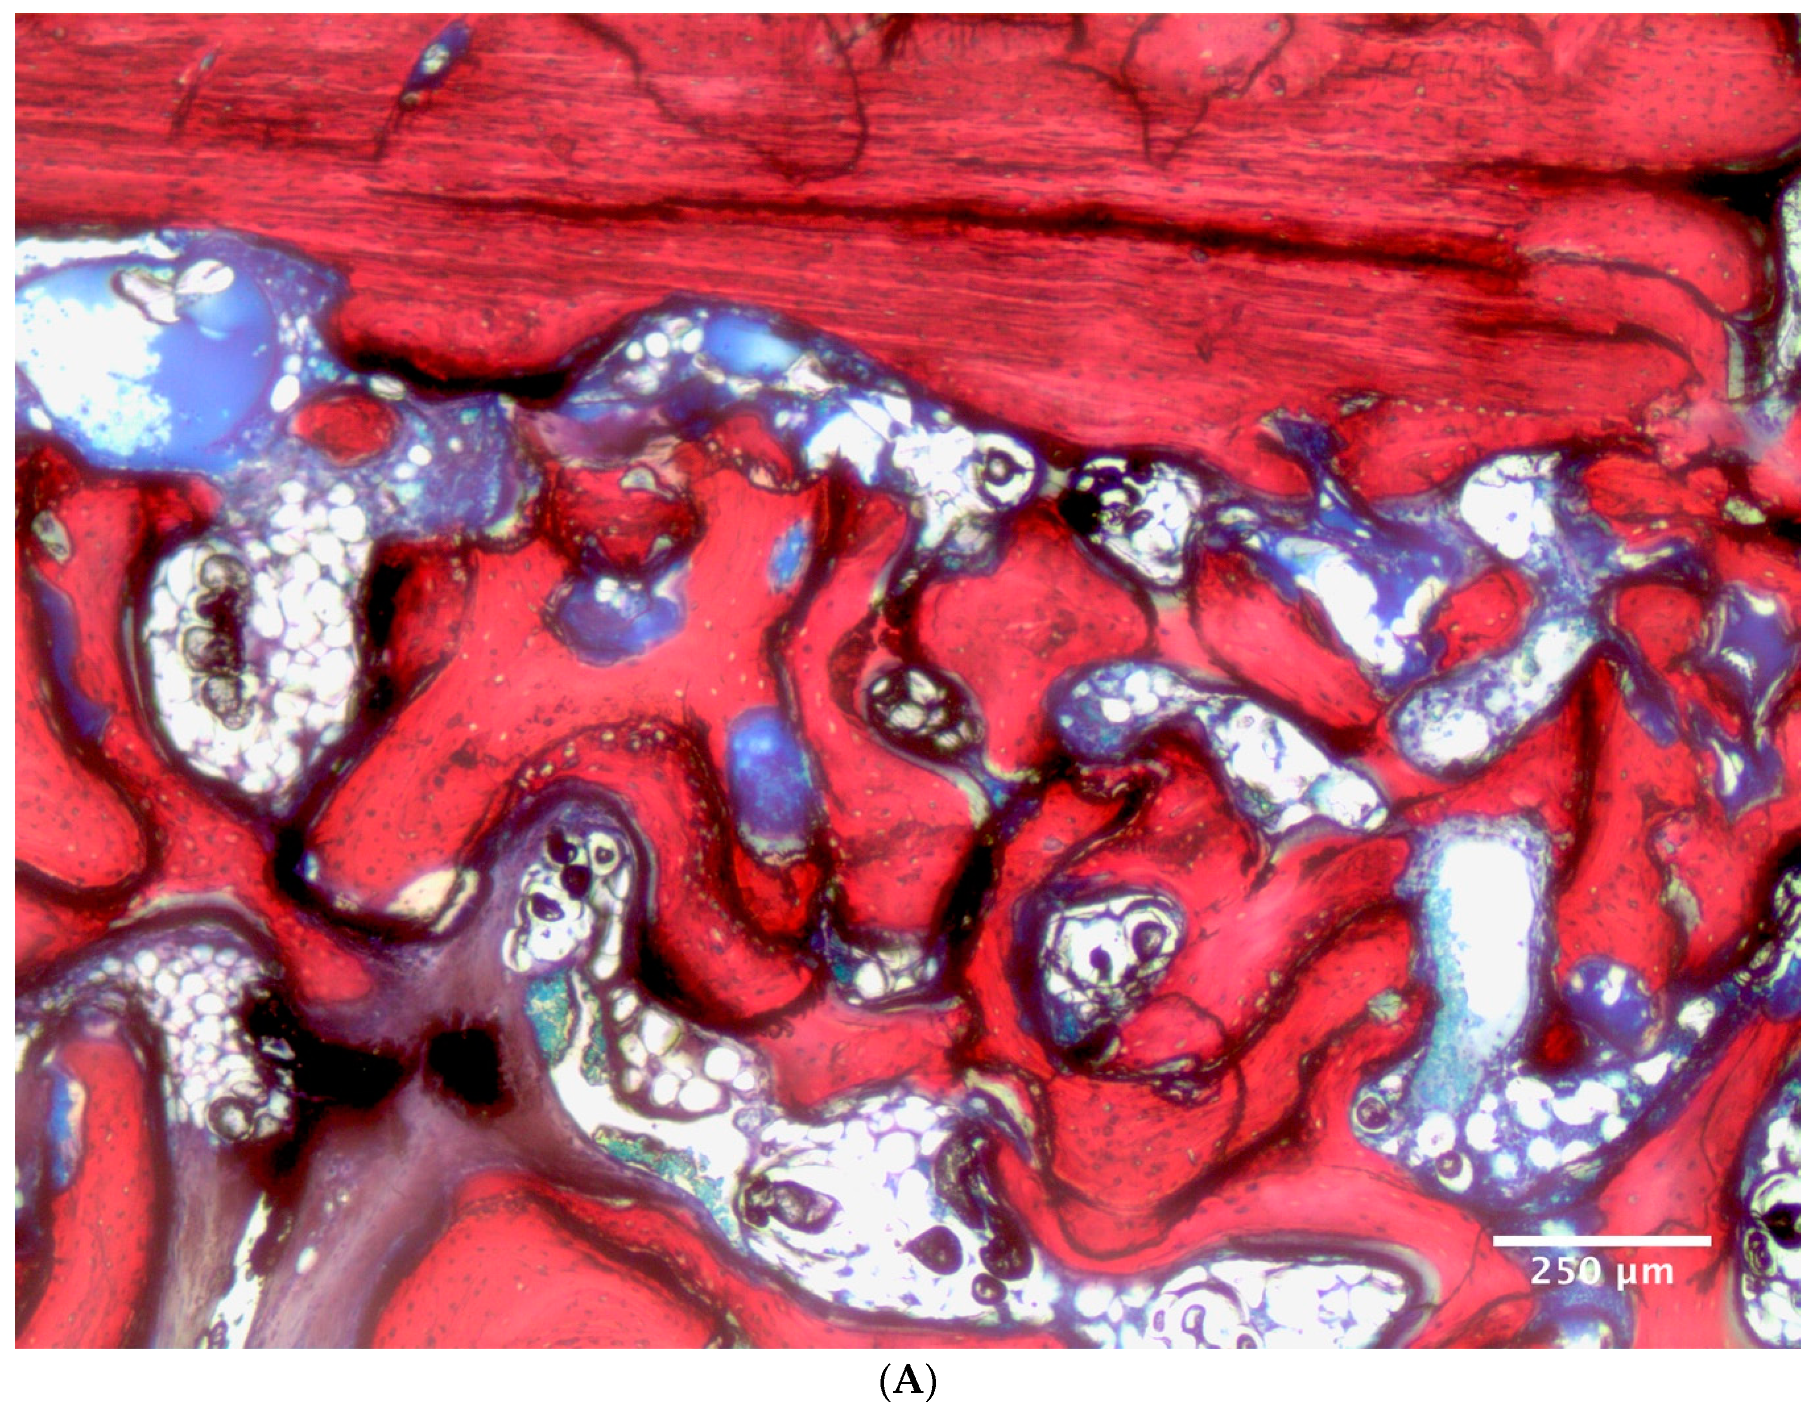

2.10. Histological Preparation and Histomorphometric Evaluation

| NFB | BMSC | 16.0 ± 6.1% | 7.8 ± 6.7% | 11.9 ± 7.5% A |

| ATSC | 9.9 ± 5.4% | 5.3 ± 5.2% | 7.6 ± 5.6% B | |

| MEAN | 12.9 ± 6.4% a | 6.6 ± 5.9% b | - | |

| XRP | BMSC | 20.7 ± 9.9% | 24.1 ± 7.0% | 22.14 ± 8.5% A |

| ATSC | 15.2 ± 4.9% | 28.0 ± 6.3% | 21.6 ± 8.5% A | |

| MEAN | 17.9 ± 8.1% a | 26.1 ± 6.8% b | - | |

| NMT | BMSC | 63.4 ± 10.5% Bb | 68.3 ± 10.3% Aa | - |

| ATSC | 74.8 ± 7.4% Aa | 66.7 ± 7.4% Ab | - |